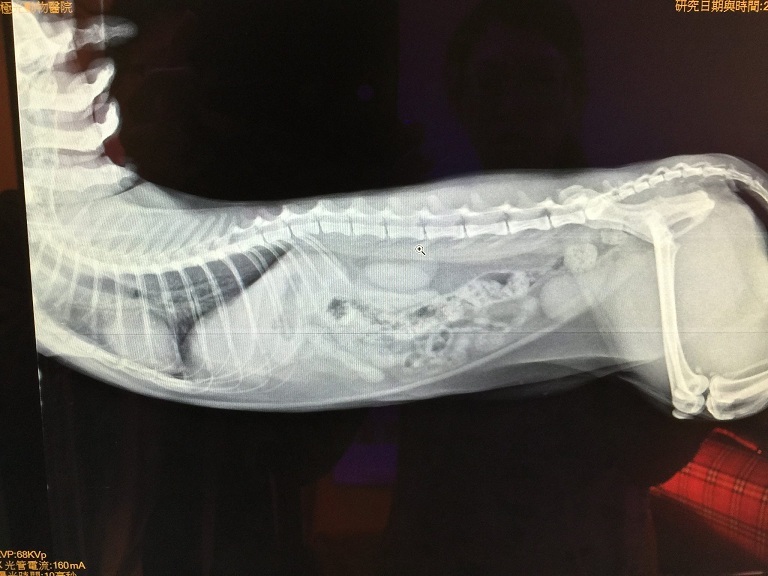

在血檢報告中,

主要是因為嘔吐的關係導致血紅素稍高,

另外腸胃有發炎反應加上鉀含量偏低,

而X光照片則沒有發現有吃進異物的跡象,

故醫生除了開抗生素、鉀片和止吐藥之外,

另外針對腸胃發炎開了一瓶胃乳,

每日早晚各一次1ml。